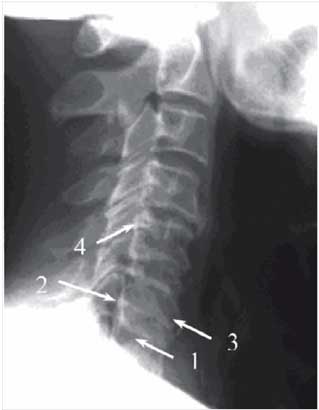

| 14:29, 14 августа 2017 | Bol spina14.jpg (файл) | 10 КБ | Рентгенография шейного отдела позвоночника. Отмечается субхондральный остеосклероз (1), снижение высоты межпозвоночного промежутка (2), ф… | 1 | |